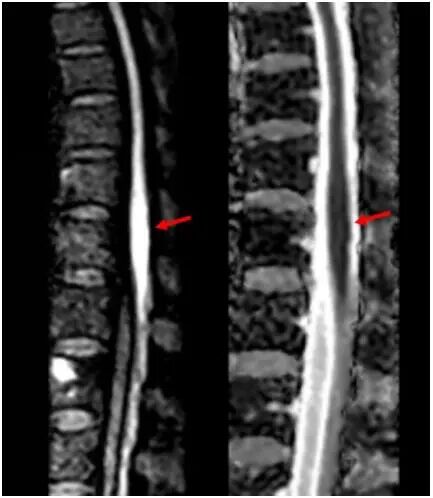

神经内科团队接诊后,凭借丰富临床经验,高度怀疑脊髓梗死。患者住院第2天早上,双下肢剧烈疼痛,很快完全瘫痪。主管护师逯红专查看患者后呼叫卒中救治团队。神经内科副主任医师刘效辉判断患者腰段脊髓再次梗死,科室迅速启动院内卒中绿色通道。医学影像科技师李峥根据神经系统查体确定的病变位置,调整扫描参数后对患者完善相关检查,磁共振影像结果显示患者脊髓圆锥存在弥散受限异常信号。医学影像科主任医师修建军阅片,确诊为脊髓梗死。超声医学科副主任医师包守刚进行超声检查排除主动脉夹层可能。

磁共振显示脊髓圆锥弥散受限,

提示脊髓梗死